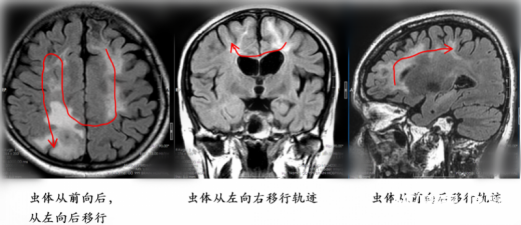

脑袋“长”虫,和饮食有关

根据复查影像,该院神经外八科二区王艮波主治医师发现虫体已转移到患者的右侧顶叶非功能区,“随访近4年,手术时机终于到了!”4月23日,神经外八科二区团队为患者行开颅手术,不仅顺利“生擒”一条20余厘米的虫子,还将“虫窝”(炎性肉芽肿)一并切除。